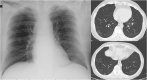

Results: We describe a 54-year-old male, hospitalized due to severe COVID-19 pneumonia. He was given long-term, high doses of systemic steroids. He developed maxillo-fascial mucormycosis and died of sepsis. Our literature search found 30 publications describing 100 patients including present case report. The majority (n = 68) were reported from India. 76% were male. The most commonly seen risk factors were corticosteroid use (90.5%), diabetes (79%), and hypertension (34%). Also, excessive use of broad-spectrum antibiotics were noted in cases. Most frequent involvements were rhino-orbital (50%), followed by rhino-sinusal (17%), and rhino-orbito-cerebral (15%). Death was reported as 33 out of 99 patients (33,3%).